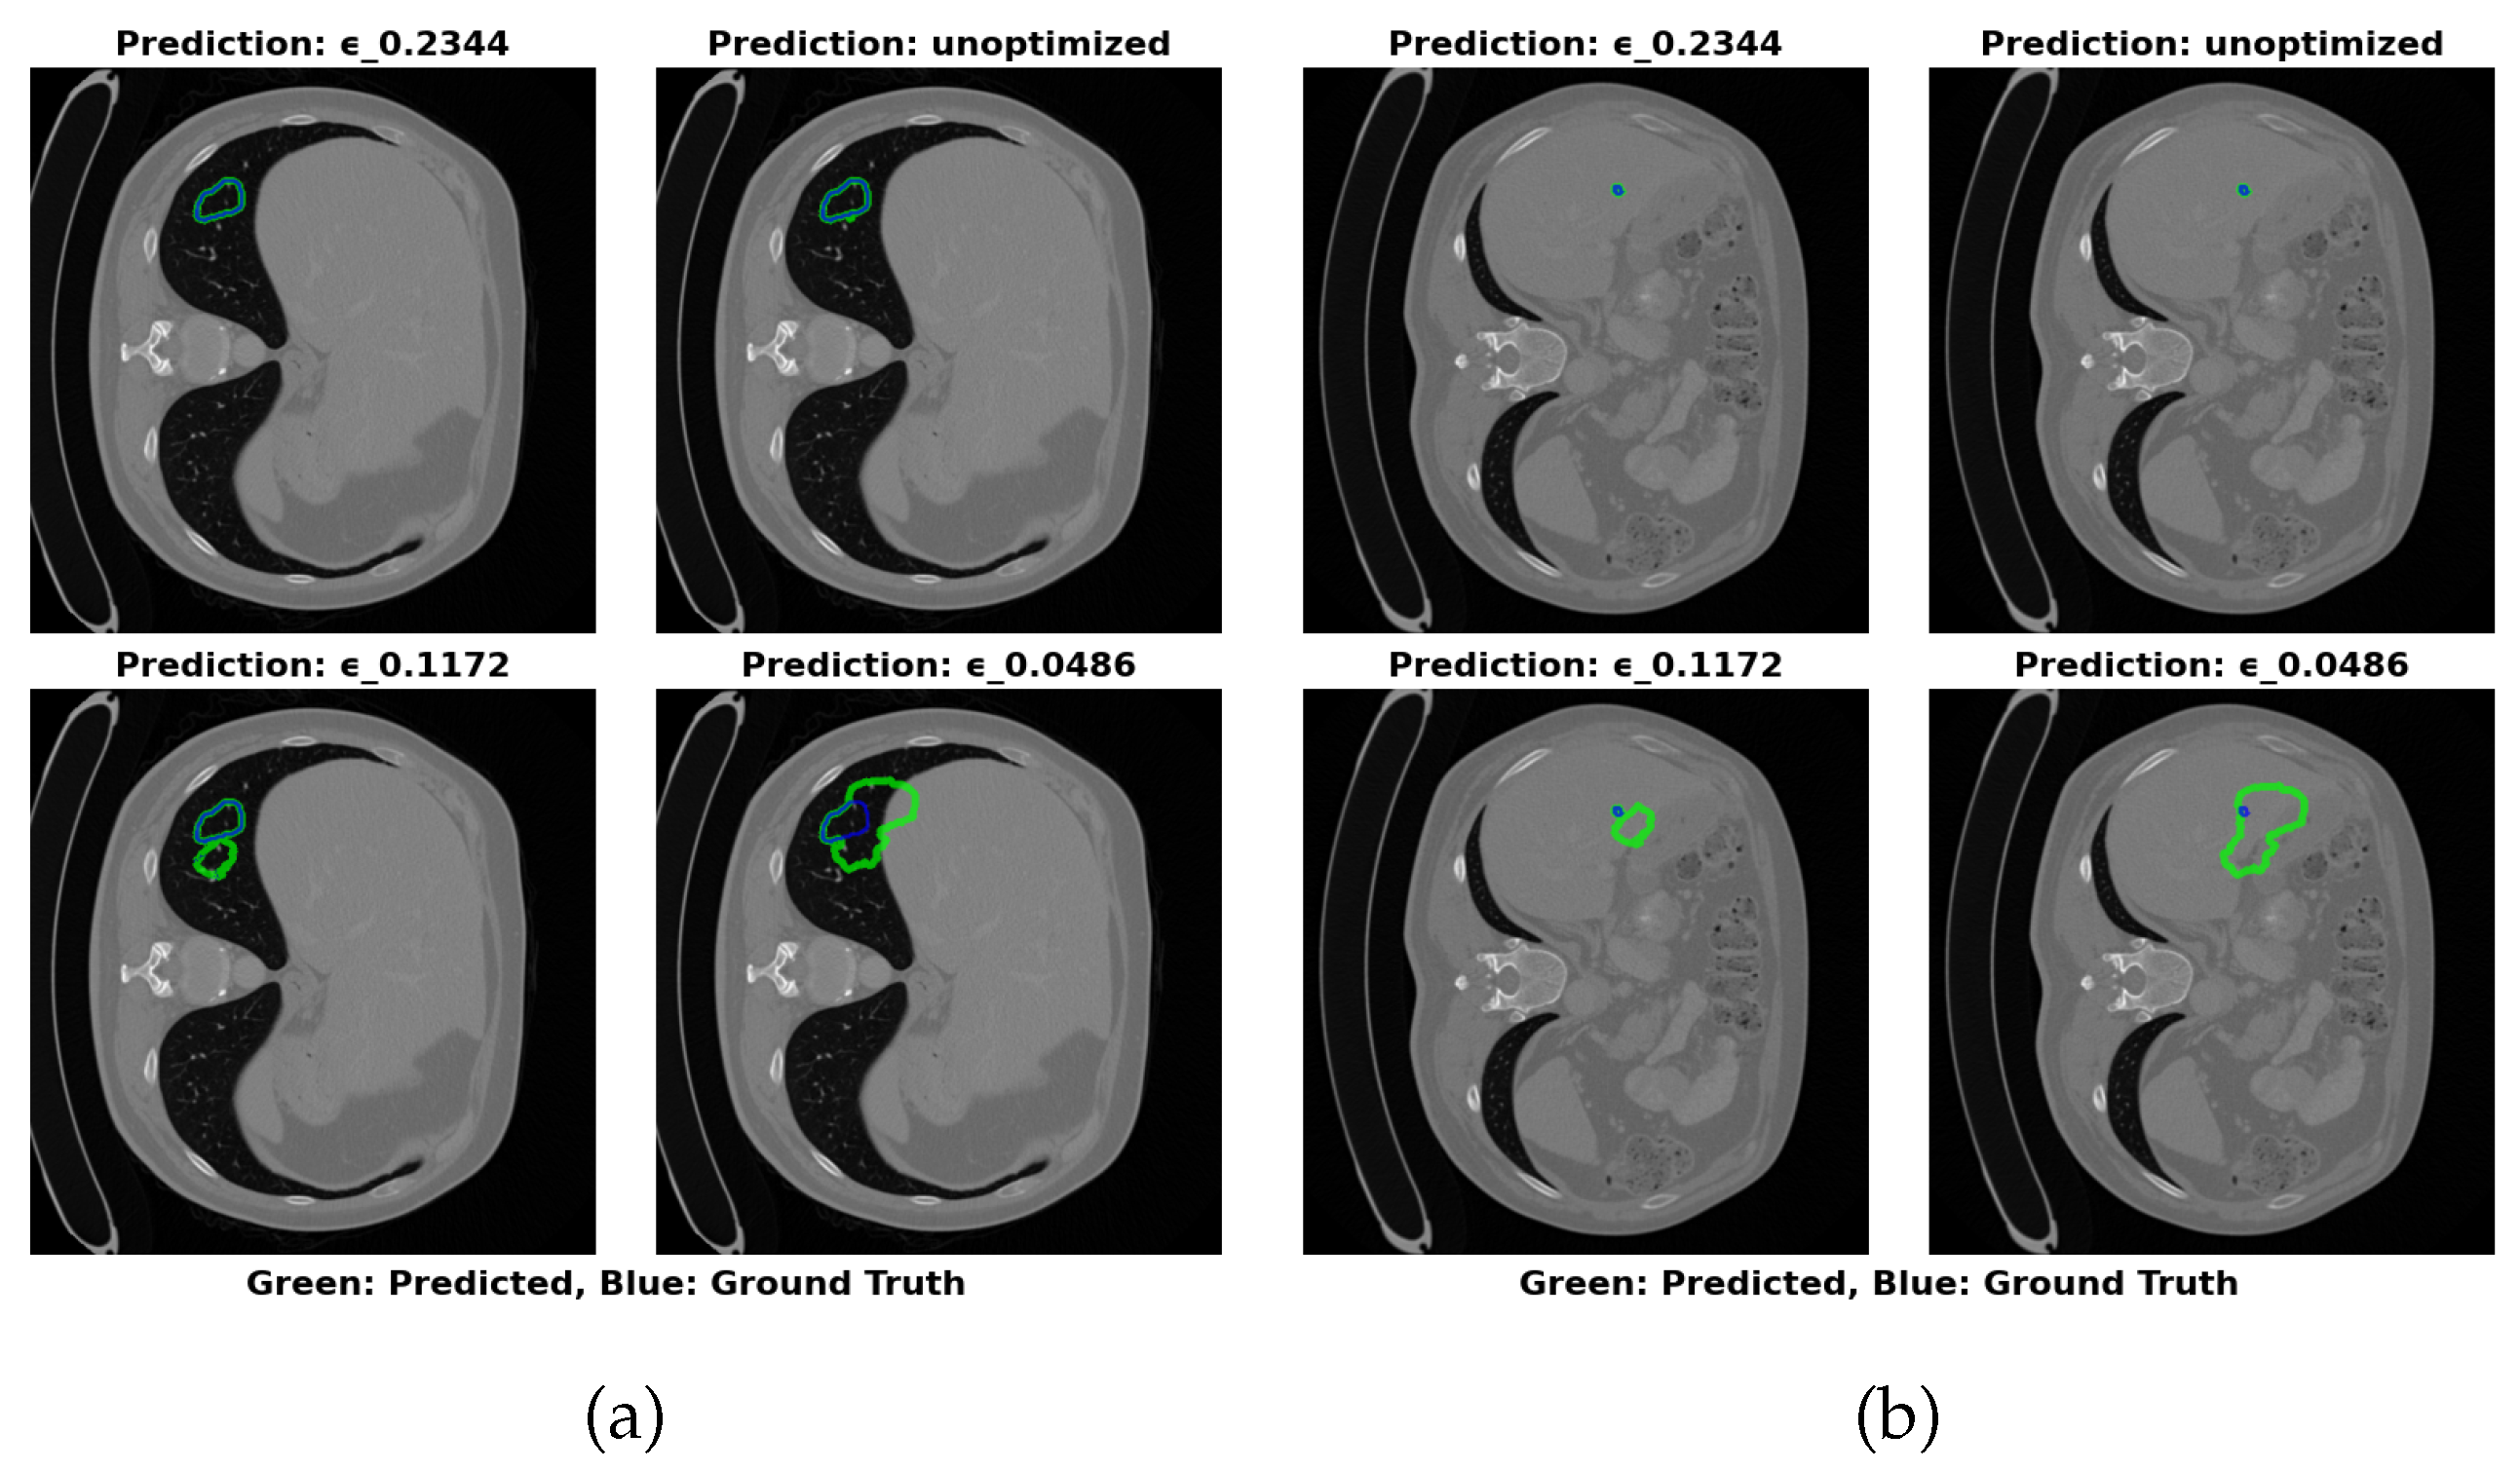

As with the 3DIRCADb dataset, reducing ϵ enhances recall but at the expense of precision, resulting in larger errors in volume estimation. The model becomes more sensitive to liver tumor pixels, but this increased sensitivity also leads to a greater number of false positives. Figure 5 shows that the optimal configuration at ϵ =0.2344 offers the most accurate segmentation boundaries, with slight deviations from the true tumor boundaries. The lower ϵ configuration (0.0486) results in larger inaccuracies in boundary delineation, supporting the need for careful selection of ϵ to balance performance and model size.

Figure 5. Visual Results of Segmentation with Different ϵ Values on LiTS17 Dataset

Preprints 152082 g005